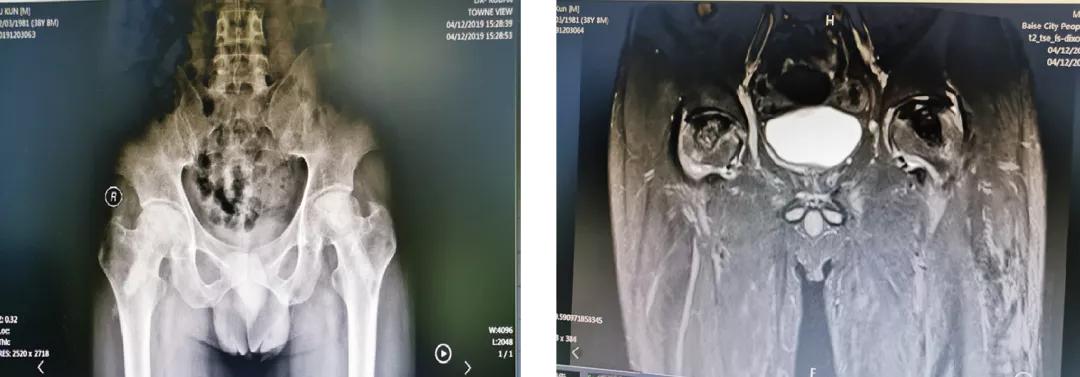

案例一

云南的苏先生今年38岁,出现双侧髋关节疼痛、活动受限1年多,被 明确 诊断为“双侧股骨头坏死”,坏死处于ARCO分期3期。在当地医院使用多种办法治疗,无明显效果,而后转到百色市人民医院关节与运动医学科。在患者及其家属强烈的保髋欲望下,科室选择了骨科机器人辅助下的微创保髋治疗,术后效果良好,患者满意。

术前辅助检查